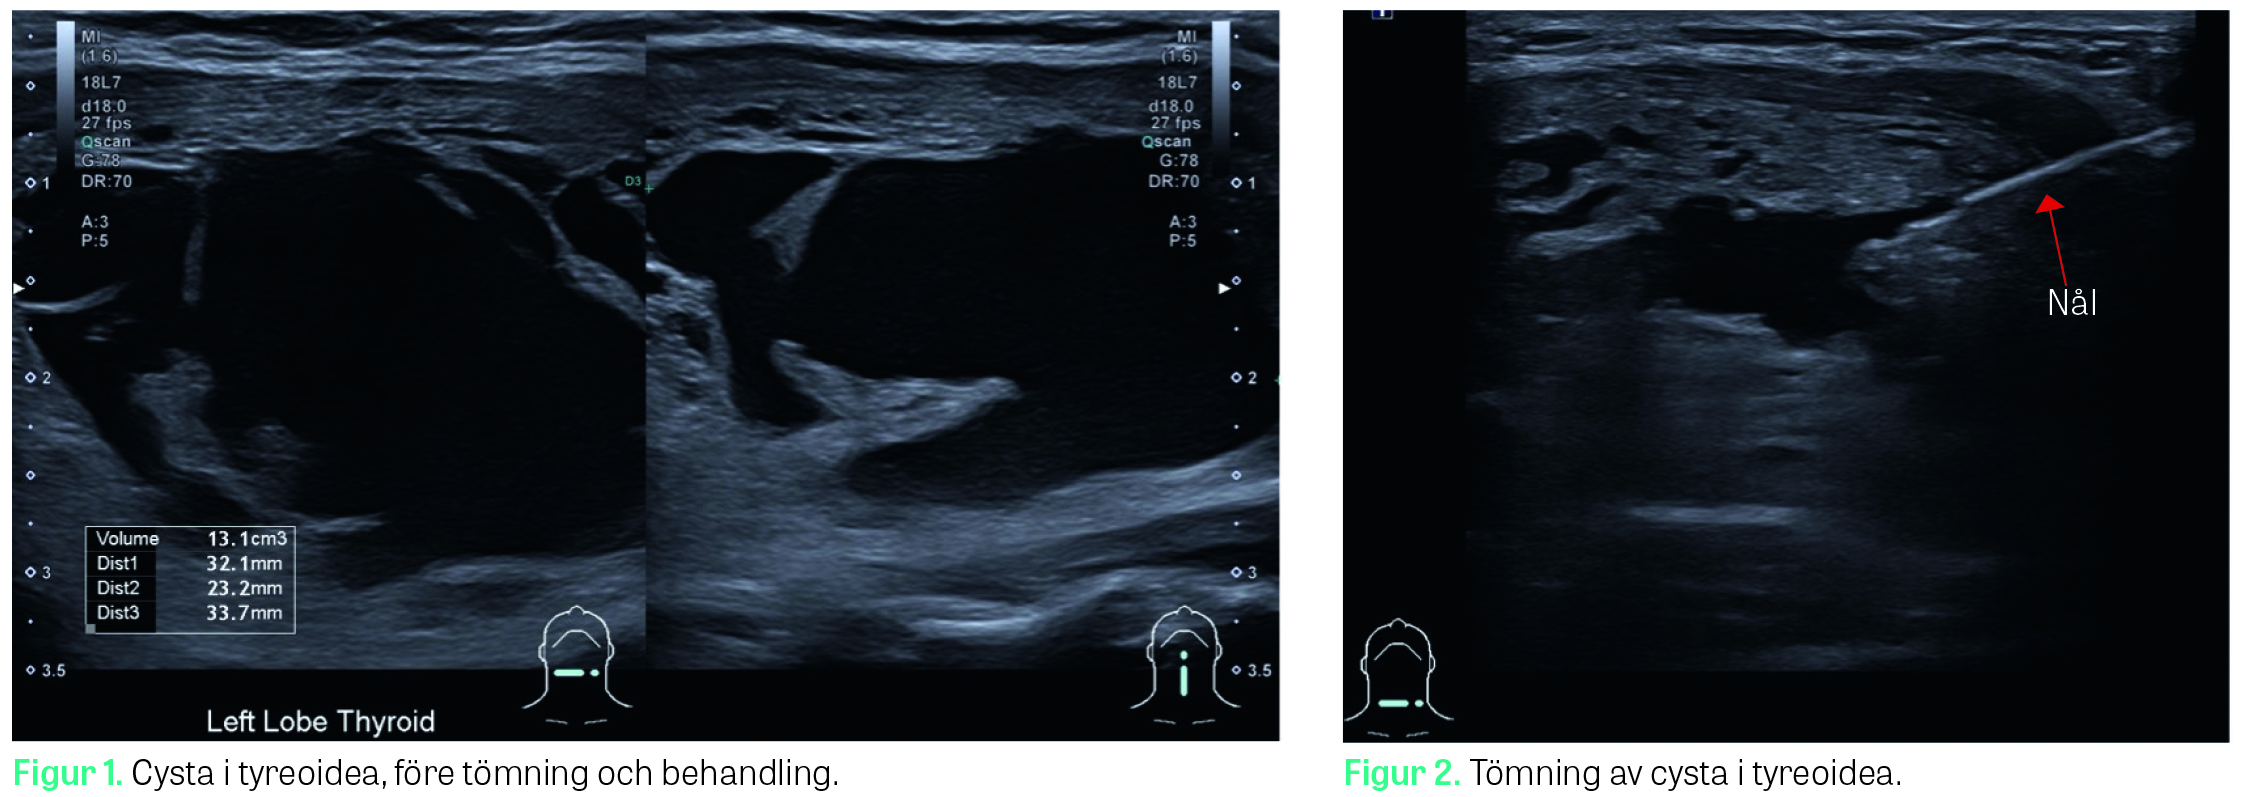

Cystans volym beräknades efter ultraljudsmätningar i tre axlar enligt följande formel: Volym = l × b × d × (π / 6), där l = längd, b = bredd och d = djup. Mätning och volymberäkning framgår av Figur 1, medan tömning av cysta via finnålsaspiration visas i Figur 2.